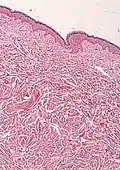

- Connective tissue nevi

- Histological test